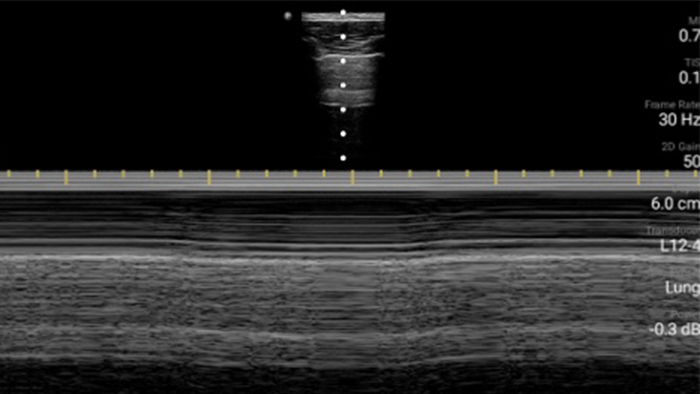

Esté atento a la neumonía por COVID

Lumify puede ayudar a obtener resultados similares a los de una tomografía computarizada de tórax al evaluar la neumonía y el síndrome de dificultad respiratoria en adultos.